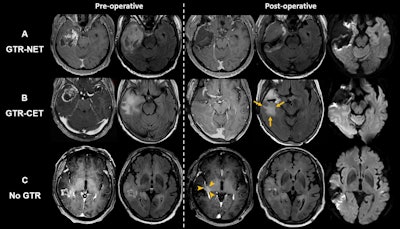

Axial MRI scans show extent-of-resection groups for (A) gross total resection (GTR) of both contrast-enhanced tumor (CET) and noncontrast-enhanced tumor (NET) (GTR-NET), (B) GTR of CET but NET remained (GTR-CET), and (C) no GTR. Scans show (B) residual T2 and fluid-attenuated inversion recovery (FLAIR) high-signal infiltrative tumor (arrows) and (C) residual CET around the surgical cavity (arrowheads). Diffusion-weighted imaging (right-side column) was used to differentiate residual T2-weighted or FLAIR signal hyperintensity as a result of NET from cytotoxic surgery-induced changes. Images and caption courtesy of the RSNA.Axial MRI scans show extent-of-resection groups for (A) gross total resection (GTR) of both contrast-enhanced tumor (CET) and noncontrast-enhanced tumor (NET) (GTR-NET), (B) GTR of CET but NET remained (GTR-CET), and (C) no GTR. Scans show (B) residual T2 and fluid-attenuated inversion recovery (FLAIR) high-signal infiltrative tumor (arrows) and (C) residual CET around the surgical cavity (arrowheads). Diffusion-weighted imaging (right-side column) was used to differentiate residual T2-weighted or FLAIR signal

hyperintensity as a result of NET from cytotoxic surgery-induced changes. Images and caption courtesy of the RSNA.